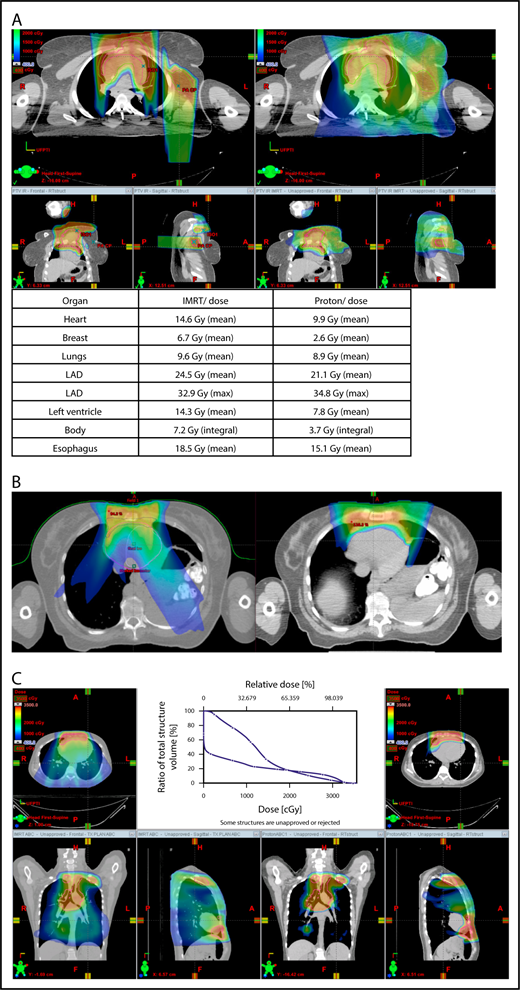

The plan target is the CTV; when the treatment area is affected by breathing motion, the plan target is the internal target volume (ITV), which encompasses the motion of the CTV depicted on 4D CT scans. Alternately, if treatment is to be given with DIBH, an ITV can be derived from the positions of the CTV reproduced from multiple DIBH scans. For lateral beam shaping, margin expansion to form the PTV accounts for setup uncertainty, and interfractional variability in anatomy is applied to the CTV/ITV. Patient-specific beam collimators conform the dose laterally to the PTV, with a margin for penumbra. Depending on the target depth and adjacent tissue, these margins vary from 5 to 10 mm. Range compensators are designed for each beam to conform the dose distally to the CTV/ITV. Range compensator smearing within a radius appropriate for setup tolerances and tissue motion is applied to account for proton range changes caused by density changes in the beam path. In addition, along each beam, distal and proximal margins are set to the CTV/ITV to compensate for proton range uncertainties, as described under “Range uncertainties due to density variations.” Multiple beams (compared with 1 beam) can be used to increase dose conformality and reduce dose uncertainties by spreading the beams in various directions. The preference is to use anterior or posterior fields, rather than both, because of the need to avoid unnecessary beam through the heart (Figure 4).

An example of an approach using 2 anterior fields with proton therapy, which can better spare the heart and esophagus (right) compared with an anterior/posterior approach (left).

With regard to field arrangements, the PBSPT technique for an anterior upper mediastinal and lower neck target usually requires 1 (repainted) or 2 anterior fields. For more complex target volumes, targets can be divided into 2 or more parts (eg, neck CTV, mediastinal CTV, and axillary CTV), and a multifield plan can be used (Figure 5). For cases that involve lower (posterior) and upper (anterior) mediastinal targets, a combination of posterior and anterior fields can maximally spare the heart and lungs (Figure 6). For upper neck targets, lateral or posterior fields can avoid the oral cavity/salivary structures. For axillary targets, a posterior field can help to spare breast tissue. Although these various field arrangements can be used in PSPT, gradient matching is simpler in PBSPT when the fields overlap or oppose, obviating the need for feathering.

Plans for PBSPT with a single-field uniform dose and a gradient match, with anterior and posterior beams used to treat disease that involves the bilateral upper neck and the mediastinum (disease anterior to the right heart).

Scans for a young woman in whom the target included mediastinal, left parasternal, and left axillary regions. One anterior field was used for the mediastinum, and a separate posterior field was used for the axillary region.